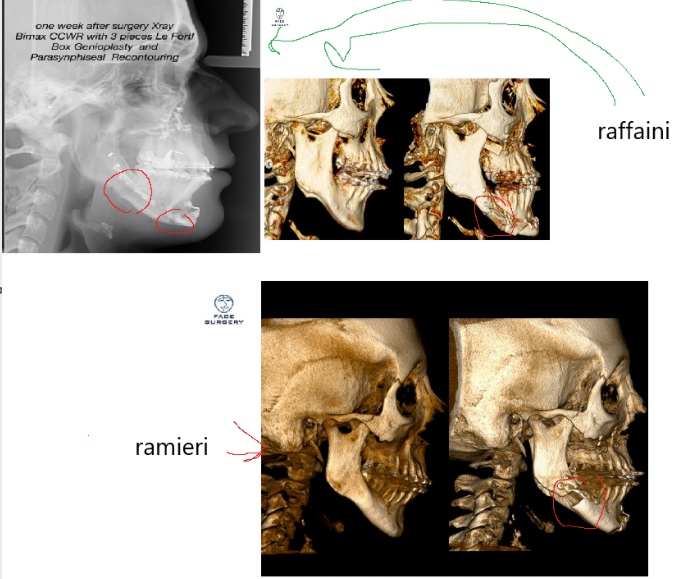

look in the pic below for example at the cuts shown with red circle:

raffaini doing big bonegrafts

look in the pic below for example at the cuts shown with red circle:

raffaini doing big bonegrafts